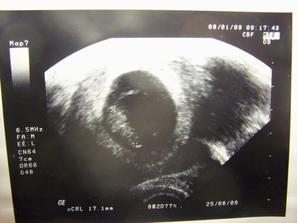

Tak po 2 letech snažení se nám povedl zázrak, museli nám pomoci v CARu a my jim za to velice děkujeme. Celou dobu nás pronásleduje číslo 2 či 22, co to asi znamená?? Jak vše začalo: 22.7. první návštěva CAR, 22.9. návštěva genetického oddělení, 22.10. výsledky genetiky, vše v pořádku🙂, 11.11.-20.11. stimulace Puregon, Orgalutran a Ovitrelle, celkem 16 injekcí do faldíku.....18.11.druhý UTZ zjištěno, že se fláká pravý vaječník, přidány jednotky Puregonu..... 20.11.třetí UTZ se nám to dle citace MUDr. krásně rozjelo a stanovený termín OPU 22.11......22.11. sobota venku krásně prvně sněží, říkám si snad štěstíčko🙂 a MUDr. mně oznamuje odebráno 29 folíků, z toho 22 oocytů, 18 zralých (12 OK + 1), 4 ihned zamraženy a zbytek na kultivaci, náběh na OHSS, prodloužená kultivace.....27.11. ET 1 embryjko (3 zamraženy).....dlouhé čekání (Čekání vyplněno 5.12. streptokokem typu A v krku). 7.12. první testík a jsou tam //. 12.12. první krev HCG 570, sestřička oznamuje do telefonu cituji....sedíte, držíte se, jste těhotná🙂..... 22.12. první UTZ 5+4 náznak srdeční akce, mimísek 2,8 mm.....8.1. druhý UTZ 8+0 mimísek 17,1 mm, srdíčko bylo krásně vidět....29.1. třetí UTZ 11+0 (nemáme fotečku☹), ale mimísek má 49,4 mm, 5 prstíčků na ručičce, nožičky jak mají bejt......12.2. NT screening 13+0, máme 73 mm a stehýnko 12 mm, máme těhotenskou průkajdu, mimísek dělal v bříšku psí kusy......6.3. poradna 16+1, vše je v pořádku.....4.4. maminka s tatínkem potvrdila společné příjmení mimíska, krásný to byl den🙂......10.4. genetický ultrazvuk 21+1....pan doktor po dlouhém hledání a zkoumání co máme mezi nožkama, teda mimísek🙂, prohlásil, že na 85% to bude holčička. Nechtěla se ukazát, je to stydlínek po mamince, tak doufáme, že se Apolenka potvrdí a mámě s tátou se splní další ze snů. Apolenka váží 420 g a vše dopadlo na jedničku.....7.4. cítíme pohyby, i tatínek už cítil🙂.....16.4. maminka začíná chodit s Apolenkou cvičit.....7.5. poradna......14.5. OGTT .....26.5. máme těhotenskou cukrovku a méně plodové vody, podstupujeme neplánovaný UTZ, Apolenka je potvrzená na 100% a má 992 g a jsme týden pozadu, návštěva obvodní lékařky, natočeno EKG a maminka má možnou hypertrofii levé komory.....28.5. návštěva diabetologie, nafasovaný glukometr, začínáme měřit a držet dietu, máme hlad a chuť🙂....29.5. poradna, začínáme být více hlídané, kontroly budou co 14 dní a máme od 1.6. neschopenku.....9.6. UTZ......11.6. ECHO srdce.....12.6. poradna....stále jsme hlídané....7.8. v pátek jsme se dověděly, že v pondělí 10.8. budu vyvolávat. V sobotu 8.8. jsem uklízela a doufala, že třeba se porod rozběhne sám. Aaaaa ve 23,30 hod přichází první kontrakce, ve 4,30 hod odjíždíme do Podolí. Jsem otevřená na 8 cm, úžasná zpráva🙂. Apolenka se narodila v neděli 9.8.2009 v 6,38 hod. Porod byl kraťoučký a Apolenka je hezoučká🙂